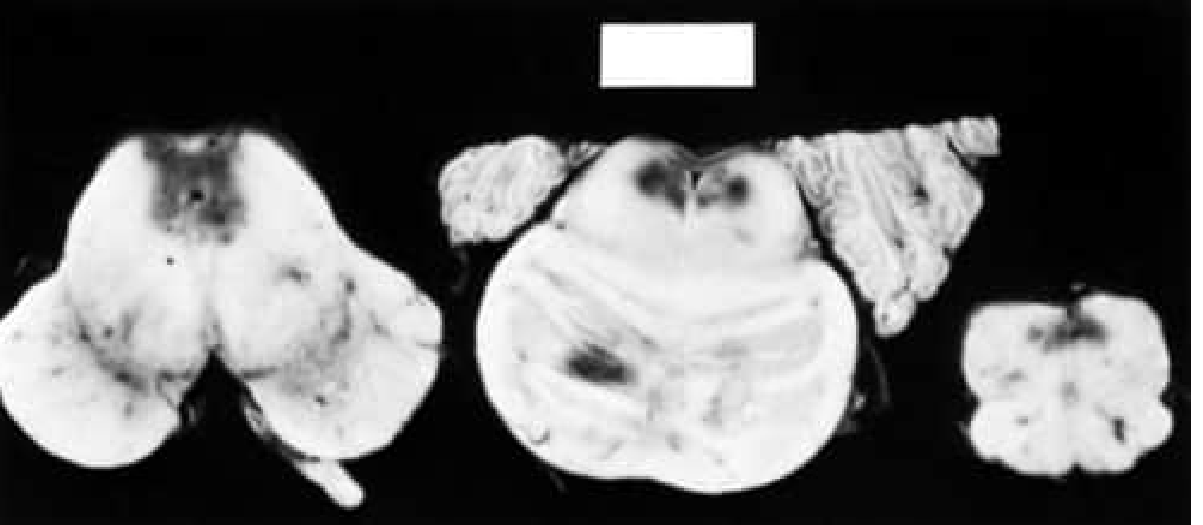

Acute Wernicke Disease — Hemorrhagic areas adjacent to the 4th ventricle and aqueduct (medulla, pons, midbrain)

Fig. Acute Wernicke Disease: Hemorrhagic areas are seen adjacent to the fourth ventricle and aqueduct in the medulla, pons, and midbrain — Bradley & Daroff's Neurology in Clinical Practice

Lesions are symmetrically distributed around:

• Periaqueductal gray matter

• Medial thalami

• Mammillary bodies

• Cerebellar vermis and dentate nuclei